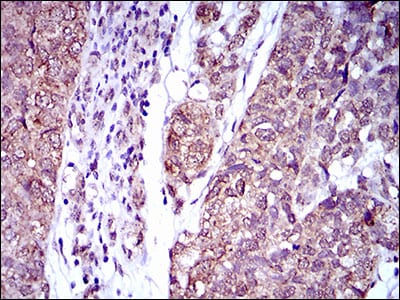

| IHC | 1/200 - 1/1000 | Human,Mouse,Monkey,Rat |

The interleukin-2 receptor alpha (IL2RA), also known as CD25. is a key component of the high-affinity IL-2 receptor complex, which regulates immune cell activation and tolerance. Primarily expressed on regulatory T cells (Tregs), activated effector T cells, and some B cells, IL2RA binds IL-2 to facilitate signaling through the JAK-STAT pathway, critical for T cell proliferation, survival, and immune homeostasis. Dysregulation of IL2RA is implicated in autoimmune diseases (e.g., type 1 diabetes, multiple sclerosis) and cancers, making it a therapeutic and diagnostic target.

IL2RA-specific antibodies are widely used in research and clinical applications. In research, they help identify and isolate Tregs or activated T cells via flow cytometry or immunohistochemistry. Therapeutically, monoclonal antibodies like basiliximab and daclizumab (now withdrawn) were designed to block IL-2 signaling by targeting IL2RA, preventing T cell activation in organ transplantation and autoimmune conditions. However, their use highlighted complexities: while suppressing pathogenic T cells, they may also inhibit Treg function, potentially compromising immune balance. Additionally, IL2RA autoantibodies serve as biomarkers in autoimmune diseases. Ongoing studies explore engineered IL2RA-targeting agents to selectively modulate Tregs or effector T cells, aiming for precision immunotherapy with fewer off-target effects.